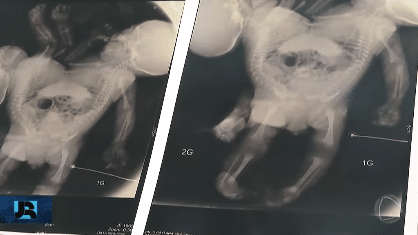

Os recém-nascidos são classificados como isquiópagos, unidos pelo tórax, abdômen, bacia e pernas. “O fígado é único, a bacia também é única, nós não sabemos ainda como é que é a parte urinária da bexiga, se elas são unidas, separadas”, explicou, ao Jornal da Record, o médico Zacarias Calil, que já atuou no parto de 46 bebês siameses e na separação de 25.

Nos próximos dias, os irmãos passarão por uma nova intervenção cirúrgica para corrigir uma má formação no intestino. A complexidade da futura separação exige um longo período de preparo. “A cirurgia de separação dos gêmeos pode acontecer daqui um ano, de acordo com os médicos, dependendo do desenvolvimento das crianças”, informou o hospital.